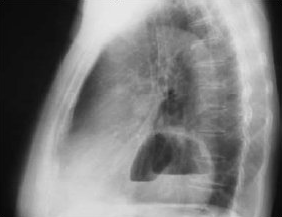

Diagnóstico y estudio

Para la confirmación diagnóstica se debe realizar una radiografía de tórax, en la que se puede encontrar sombra retrocardiaca. El uso de contraste es necesario para demostrar el tipo de hernia, el tamaño y la anatomía gástrica. Una hernia por desplazamiento se caracteriza por una distancia mayor a 2 centímetros entre el anillo correspondiente a la línea Z y el hiato diafragmático. Se puede visualizar parte del fondo gástrico herniado al lado del esófago distal en casos de hernias paraesofágicas.